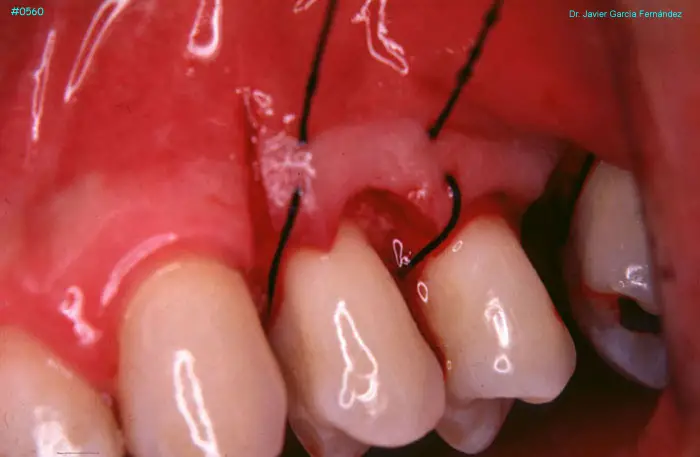

Atlas of Surgical Techniques in Periodontics. Chapter II. Atlas de Técnicas Quirúrgicas en Periodoncia